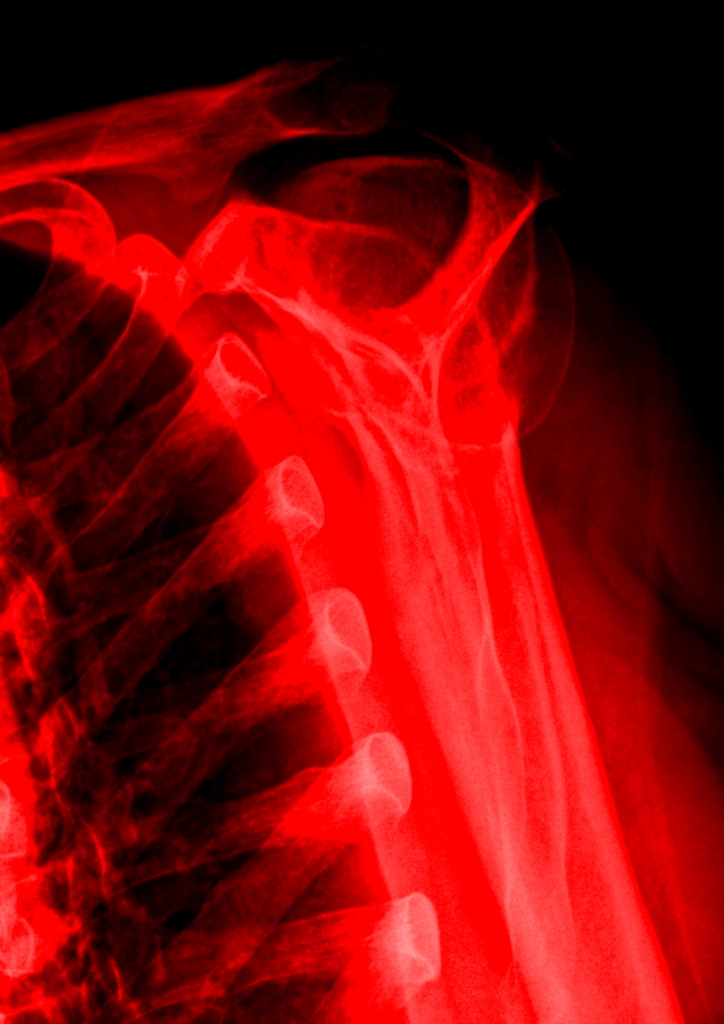

Best of all, the X-ray shoulder views are available, and simple photo-editing software–Paint and Microsoft Office Picture Manager–may be used on the images. Andy Warhol did stuff like this the hard way, back in the day. Longer ago, Robert Rauschenberg had to content himself with light-reactive paper and bright, bright light for some white-on-blue skinscapes of him and his companion. But now–colorizing, brightness&contrast, data compression and many other image-manipulative techniques are easy as pie, funfunfun, and available with the latest operating systems!

So here are four shoulderscapes. If time were not of the essence I would have happily spent another several hours playing with the image; alas, time is scarce. These four, though, demonstrate how color, contrast and cropping of the same subject matter might yield four quite different visual payoffs.